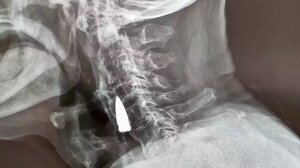

"Καρφωμένη" στο κεφάλι του 29χρονου η βολίδα - Σε κρίσιμη κατάσταση ο νεαρός ΚΡΗΤΗ 07.08.2023"Καρφωμένη" στο κεφάλι του 29χρονου η βολίδα - Σε κρίσιμη κατάσταση ο νεαρός

Ετοιμάζεται για νέα επέμβαση ο 29χρονος Νίκος με τη σφαίρα στο κεφάλι ΚΡΗΤΗ 29.11.2023Ετοιμάζεται για νέα επέμβαση ο 29χρονος Νίκος με τη σφαίρα στο κεφάλι